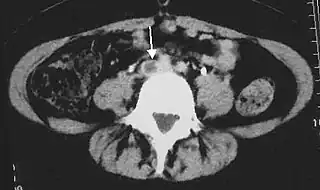

![]() Tomografía computarizada abdominal que muestra trombosis en una vena ilíaca común. La flecha indica el defecto de llenado en la vena que se visualiza usando un radiocontraste. | ||